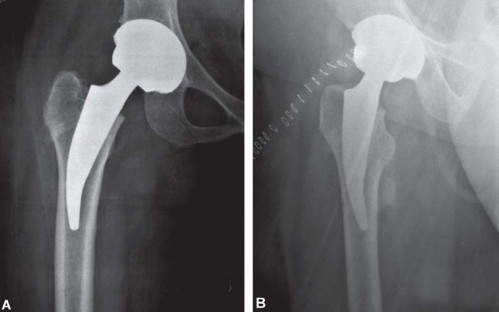

* خيار مراجعة محافظ: للمرضى الذين فشلت لديهم جراحة إعادة تسطيح المفصل.

الشرط الأساسي هو وجود عظم جيد النوعية.

لقد تم التساؤل عن دور الجذوع القصيرة في جراحة استبدال مفصل الفخذ الكلي. وتُقارن بشكل واضح مع جراحة إعادة تسطيح المفصل (hip resurfacing) وجذوع الفخذ المخروطية الحديثة غير الإسمنتية ذات نقل الحمل القريب. بينما تحافظ جراحة إعادة تسطيح المفصل على العظم، إلا أنه لا يمكن القول إنها تحافظ على الأنسجة الرخوة، حيث يكون الشق الجراحي ومدى تشريح الأنسجة الرخوة اللازم للتعرض عادة أكبر مما هو عليه في جراحة استبدال مفصل الفخذ التقليدية. علاوة على ذلك، تقتصر جراحة إعادة تسطيح المفصل على مفصل المعدن على المعدن، والذي له مجموعة مشاكله الخاصة مثل فرط الحساسية، والتهاب الأوعية الليمفاوية المرتبط بالمعادن (ALVAL)، ومشاكل الاستخدام لدى الشابات في سن الإنجاب، والمخاوف بشأن ارتفاع مستويات أيونات المعادن في الدم.

فشل الجراحات السابقة

في بعض الحالات، قد يحتاج المرضى الذين خضعوا لجراحات سابقة مثل إعادة تسطيح المفصل (hip resurfacing) إلى جراحة مراجعة إذا فشل الزرع الأولي أو ظهرت مضاعفات مثل فرط الحساسية للمعادن أو ارتفاع مستويات أيونات المعادن.